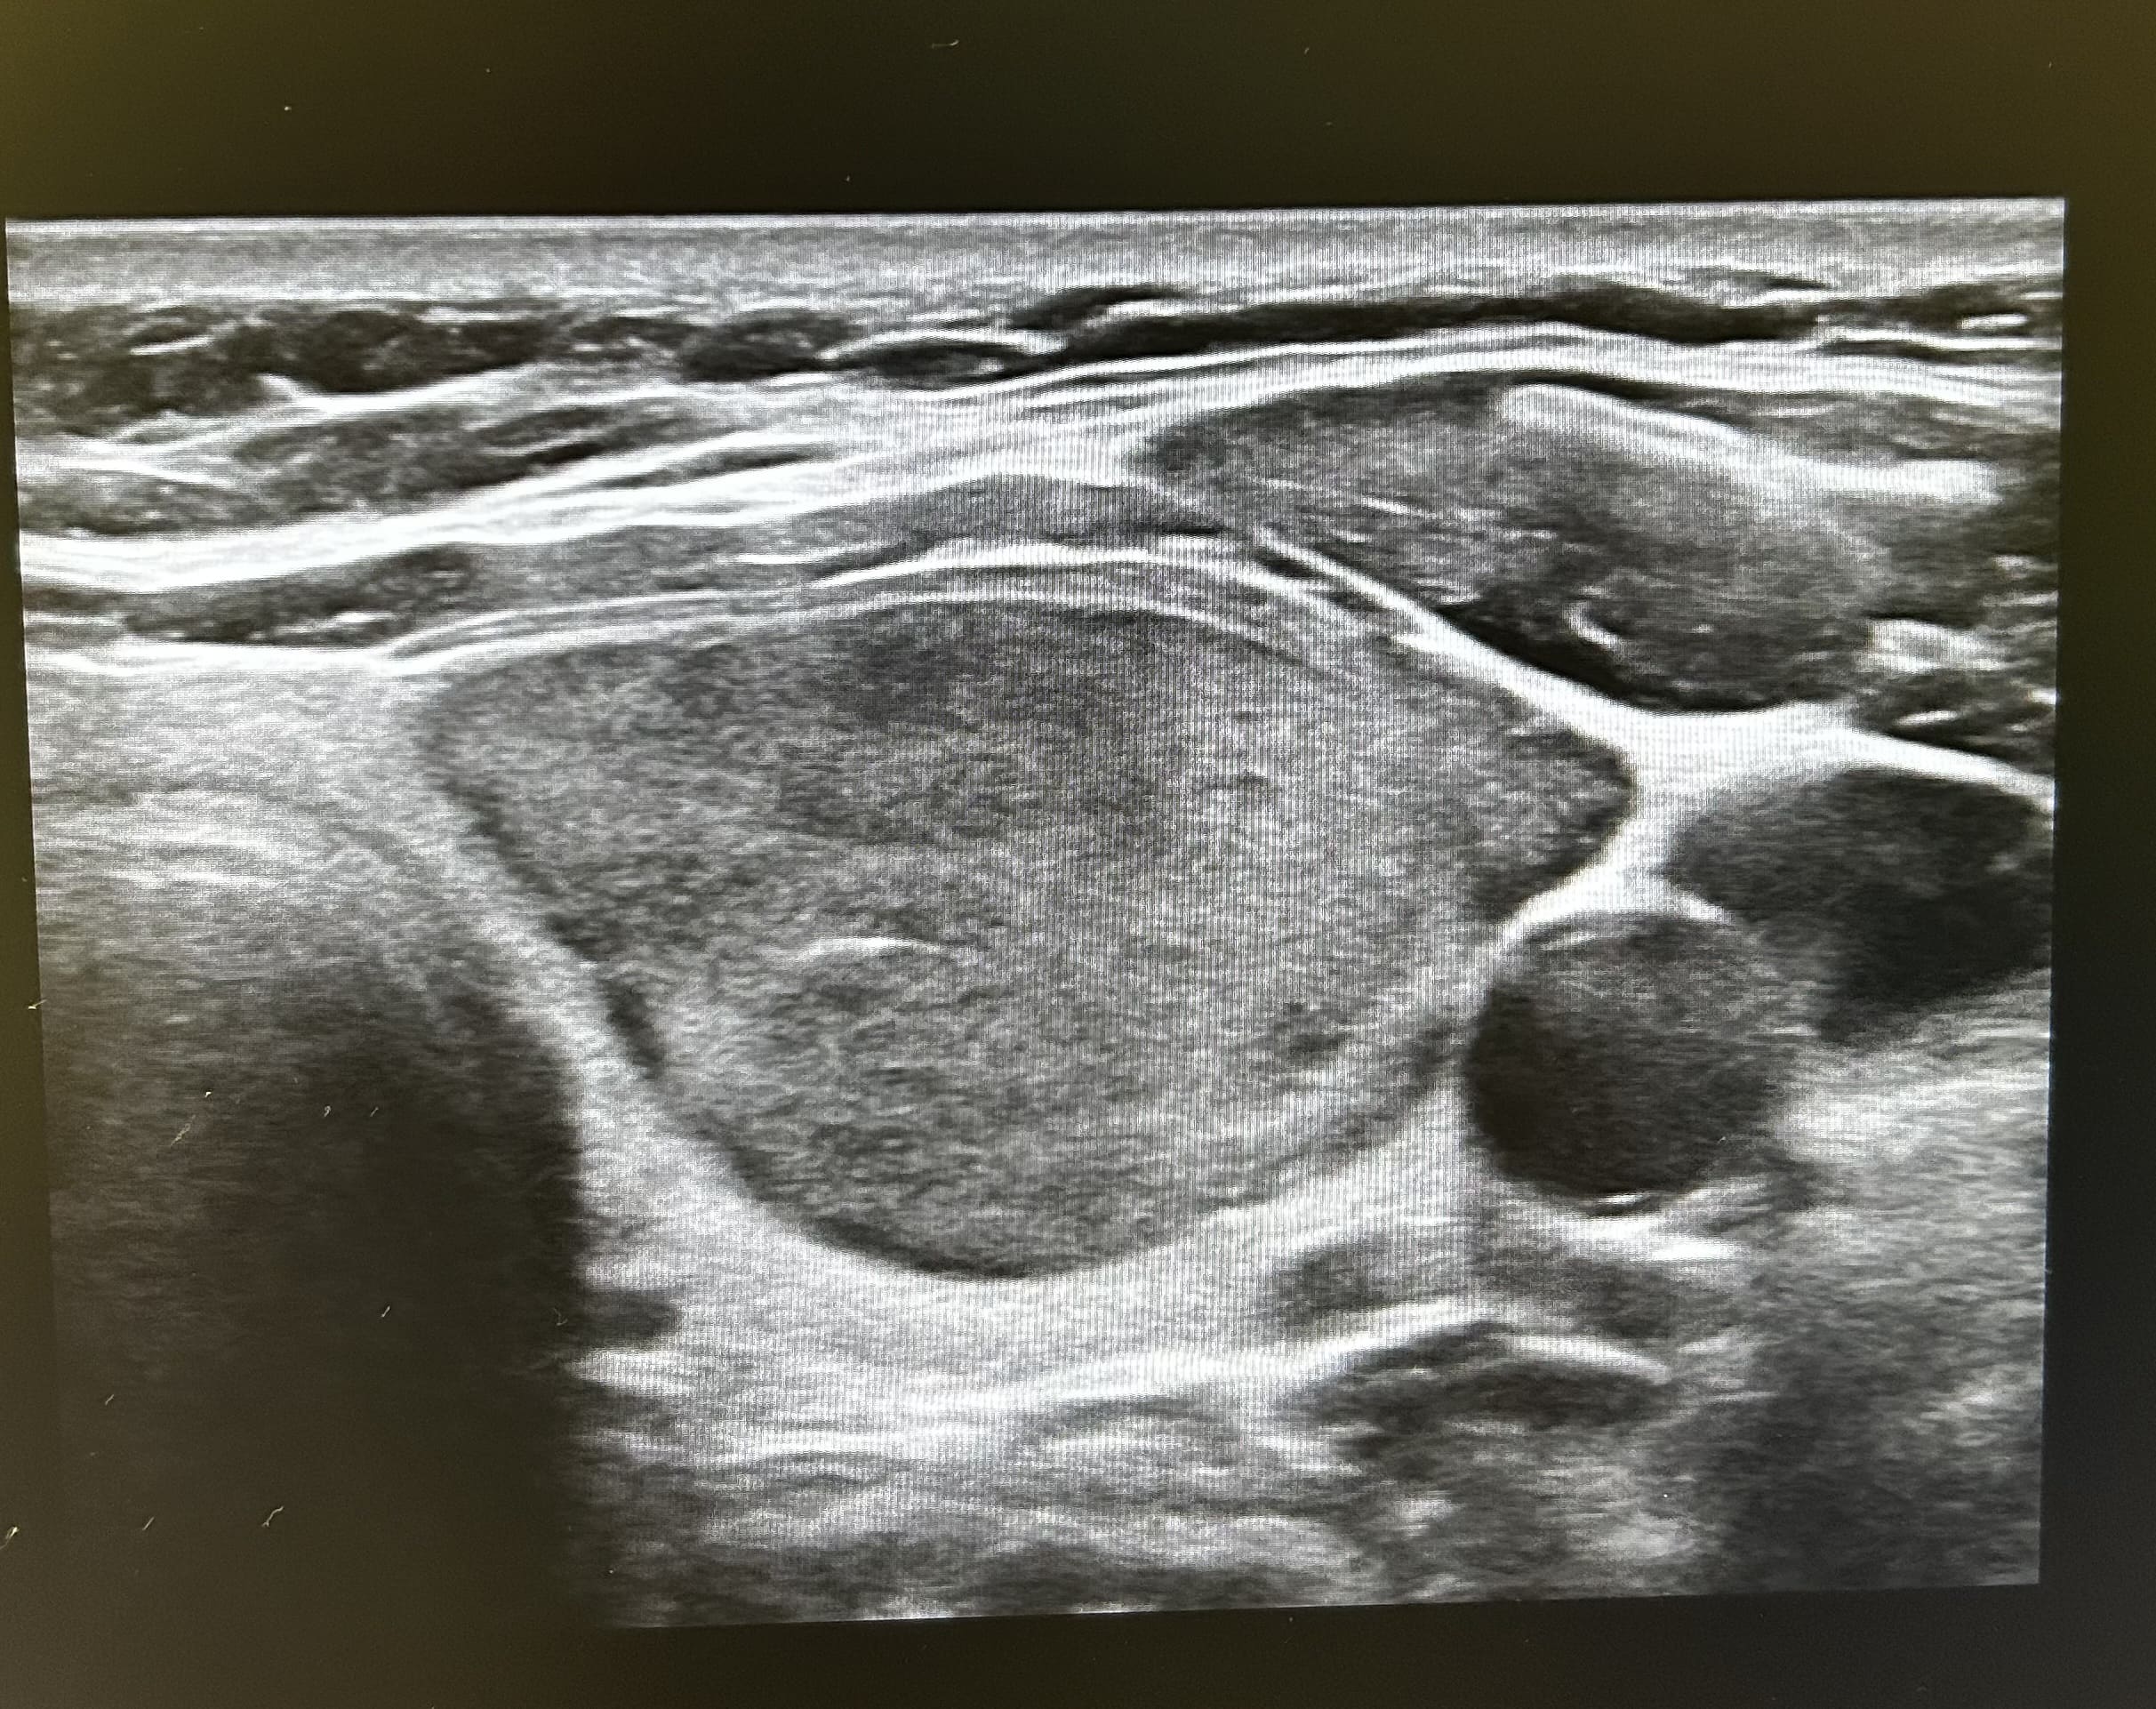

Apreciamos un nódulo tiroideo hipoecogénico y heterogéneo, de bordes irregulares y con vascularización central de 22 milímetros de diámetro mayor (transversal). Sin apreciar microcalcificaciones ni invasión de la glándula. No apreciamos adenopatías cervicales en rango patológico.

En ecografía reglada describen características similares con un TI-RADS 4, nódulo sugestivo de malignidad.